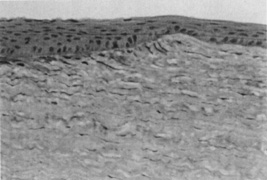

The major interest in the excimer laser has been in the alteration of the anterior corneal contour for the correction of refractive errors. Improvements in the techniques and instrumentation for PRK and LASIK have minimized the risk of significant visual loss associated with these procedures. However, irregular astigmatism or scarring secondary to the ablation, the patient's healing response, or flap complications can still occur. Epithelial hyperplasia and hypoplasia (see Fig. 7) often minimize the irregularities over time, and superficial haze after PRK often slowly fades. However, in some cases, loss of best corrected vision, multiplopia, or other optical aberrations can persist and need to be managed surgically. PTK can be helpful in the management of these complications.

Fig. 7. Normal thickness of the epithelium is seen over the untreated cornea (right). Hyperplasia of the epithelium in the ablation zone (left) approximately doubles the original corneal thickness, leading to restoration of a smooth corneal contour (original magnification ×160).